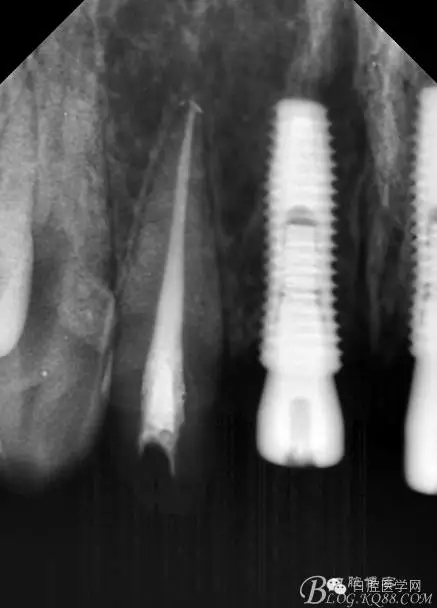

設(shè)計(jì)方案:11.21種植(選用登騰系統(tǒng),GBR植骨)12.22 RCT后樁冠修復(fù),牙齦瓷修復(fù)。

一期手術(shù)后3-6個月可做二次修復(fù),接愈合基臺,拆線后10-15天根據(jù)情況可以采模型做牙冠。